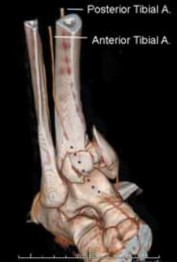

8.

E F ### FIG 4 • 43-C3 tibial plafond injury. A,B. AP and lateral injury radiographs. C. CT scan. D. “Travelling traction”—early ankle-spanning external fixator. E,F. Radiographs of ankle after closed reduction and application of external fixator. G. Three-dimensional reconstruction of CT angiogram demonstrat- G ing deficient flow through anterior tibial artery.